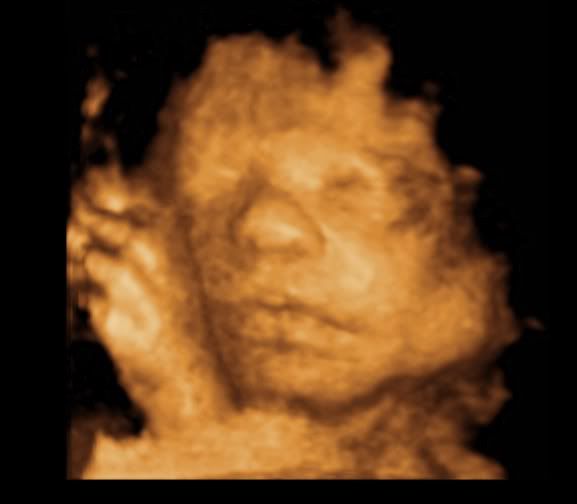

hegejenta30 Skrevet 19. mars 2011 #1608 Skrevet 19. mars 2011 Så herlige bilder av lille frøken krek! Skjønner godt du er forelsket!

Kokos Skrevet 19. mars 2011 #1611 Skrevet 19. mars 2011 Så fine bilder dere fikk! Der ser man jo vakre lille krek kjempegodt

^^Belle^^ Skrevet 19. mars 2011 Forfatter #1612 Skrevet 19. mars 2011 Så herlige bilder av lille frøken krek! Skjønner godt du er forelsket! Det gjør jeg også. Hun er jo det fiiiineste i hele verden. OOOOH, been there!!! Min var 56 cm lang da han ble født, så du kan jo tenke deg hvor deilig det var for ribsa på slutten.... Det kan jeg tenke meg. Håper ikke lille krek er så lang altså. Nusselige bilder! Takk. Så fine bilder dere fikk! Der ser man jo vakre lille krek kjempegodt Ja, noen av dem ble kjempefine. Nå gjenstår det bare å se om hun ligner på disse bildene når hun kommer ut.

Mazilla Skrevet 19. mars 2011 #1616 Skrevet 19. mars 2011 Jeg må ærlig innrømme at jeg synes alle 3D-ultralydbilder ser like ut.. Men ikke mindre koselig av den grunn, da! Kos deg i kveld! Selvfølgelig er det lov med sørlandschips på en lørdag!

^^Belle^^ Skrevet 19. mars 2011 Forfatter #1618 Skrevet 19. mars 2011 Jeg må ærlig innrømme at jeg synes alle 3D-ultralydbilder ser like ut.. Men ikke mindre koselig av den grunn, da! Kos deg i kveld! Selvfølgelig er det lov med sørlandschips på en lørdag! det har jeg også syntes frem til nå. Men vissheten om at det er vår jente vi ser...åh, jeg kan ikke la være å smile hver gang jeg ser bildene. Støttes! Og spretter i en pose med sørlandschips med spansk paprika! *mmmm* sørlandschips er bare best.

Småkjekset Skrevet 19. mars 2011 #1619 Skrevet 19. mars 2011 29 uker Så skjønn og fredfull hun ser ut Håper du får en fantastisk kveld med god snacks

Neala Skrevet 20. mars 2011 #1620 Skrevet 20. mars 2011 Åh, i alle dager, så fin hun ser ut! Tenker dere ikke gleder dere noe mindre nå